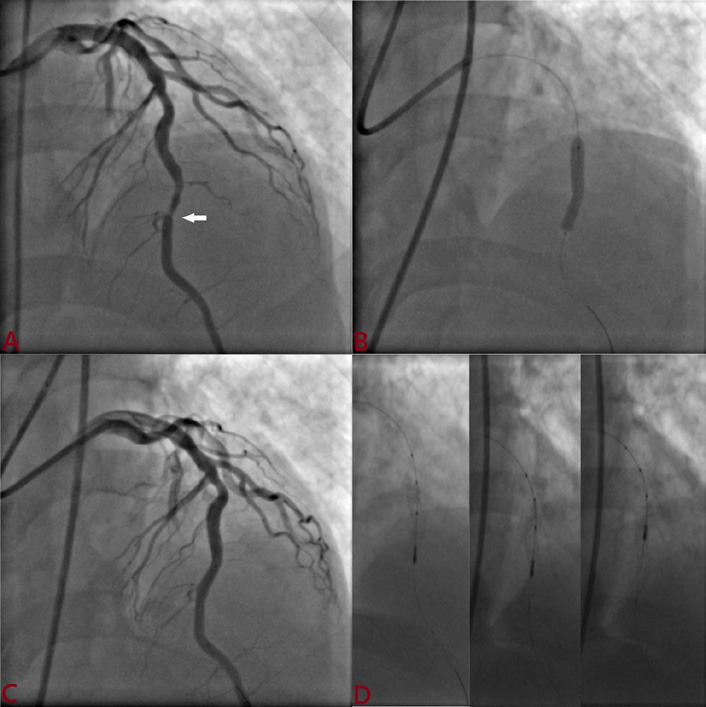

Background: Intravascular ultrasound (IVUS)-guided percutaneous coronary intervention (PCI) is useful for stent optimization. Outcomes of the ultrathin Supralimus Tetriflex stent (Sahajanand Medical Technologies Pvt. Ltd., India) using IVUS were evaluated among patients with short (≤ 20 mm) versus long lesions (≥ 20 mm).

Methods: A total of 207 patients underwent PCI, and IVUS was performed post-deployment. The primary outcome was optimal stent deployment, defined as (a) mean surface area (MSA) >5.0 mm²; (b) plaque burden <50%; (c) complete apposition; and (d) no edge dissection. Secondary outcomes were target lesion failure (TLF)-a composite of cardiac death, target vessel myocardial infarction (TVMI), and target lesion revascularization (TLR)-stent thrombosis, and major adverse cardiovascular events (MACE; a composite of death, MI, stent thrombosis, and repeat revascularization).

Results: Suboptimal deployment was significantly more frequent among patients with longer lesions (30.1% vs. 23.3%; p=0.03) due to higher rates of malapposition (17.3% vs. 10.6%) and MSA <5 mm² (9.6% vs. 7.7%). Following post-dilatation, suboptimal deployment was observed in 7.6% and 5.8% of patients, respectively. Residual plaque burden was 4.5% and 5.7%, respectively. The MSA in both groups was 6.3 mm² and 6.5 mm². Minimum and mean stent expansions were 82.1% versus 81.7% and 106.3% versus 109.8%, respectively, with no significant differences. TLF and stent thrombosis were observed in 0.9% versus 0.9% and 2.9% versus 3.8% of patients, respectively, with no significant differences. However, MACE was significantly higher (10.5% vs. 8.7%; p=0.05) among patients with longer lesions.

Conclusion: Supralimus Tetriflex stent has very good optimal deployment based on angiogram and becomes better with IVUS imaging, making it safe among long lesions (≥ 20mm).